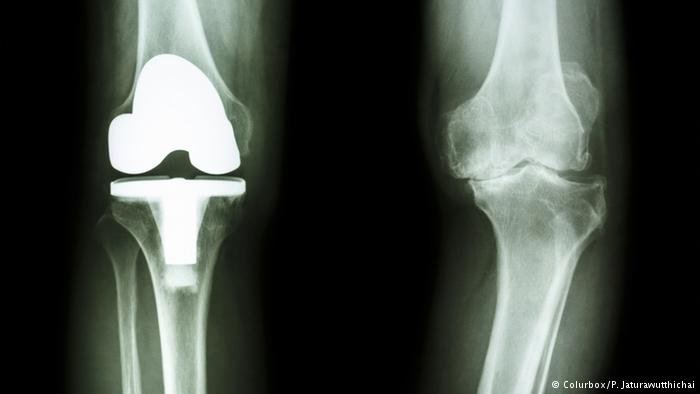

عمل جراحی تنها زمانی توصیه می‌شود که هیچ یک از روش‌های محتاطانه موثر نباشد. پیوند غضروف، پروتز و آرتروسکوپی از روش‌های موجود برای درمان به‌وسیله اعمال جراحی است. تشخیص بهترین روش درمان فقط در صلاحیت پزشک متخصص است.